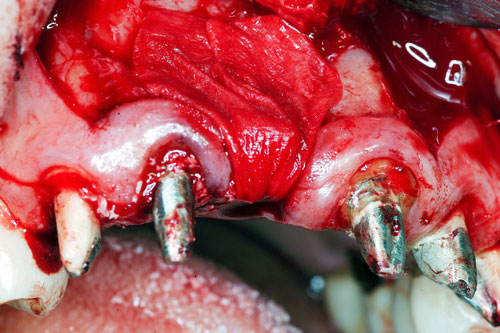

Mientras dichos movimientos ortopédicos se producen (período que supondrá otros seis meses), estudiamos los actos quirúrgicos a realizar en los cuatro implantes que pondremos. De acuerdo al estudio Desatascan realizado observamos tres situaciones diferentes: 1º-El Primer Molar Inferior Izquierdo, lo instalamos mediante Cirugía Minimamente Invasiva , con la aplicación de una Férula Quirúrgica Obtenida de los datos del scanner tratados con un programa de CMI (Cirugía Minimamente Invasiva), previa prueba en un modelo estereolitográfico, ya que la altura ósea era apenas de 9 mm. 2º- El Primer Molar Superior Derecho, se implantará mediante una ligera Elevación Atraumática (Trans alveolar) de Seno una vez logrado el espacio mesio distal necesario. 3º- El Incisivo Central Superior Derecho ausente, cuenta con un sustrato óseo prácticamente inexistente. El espesor de la tabla era de menos de 2 mm. Los caminos posibles a seguir para contar con una Rehabilitación de piezas independientes son dos: Optamos por esta segunda opción por ser menos cruenta y no necesitar de una zona dadora. Técnica esta que pondremos en práctica en dos etapas diferidas: 1º-Incisión horizontal palatinizada, incisiones peri rodetes gingivales e incisiones de descarga. Dilatación que comenzamos con dos incisiones de descarga sobre la cortical vestibular realizadas con disco. y el comienzo de la dilatación propiamente dicha mediante una hoja de bisturí, para luego seguir con un periostótomo . Recién después de alcanzada una cierta separación de la cortical vestibular de la palatina, empezamos con los dilatadores roscados. En este punto podríamos haber utilizado sin riesgos un Implante de 3,8 mm de diámetro, pero a fin de mejorar la estética del pilar emergente decidimos rellenar con material osteoconductor y osteoinductor (BiOss) y cubrir mediante membrana reabsorvible ( Bio Guide). 2º-Implantación seis meses después. Mientras se van cumpliendo los tiempos antes mencionados, y comprobamos reiteradamente la funcionalidad de la oclusión con los provisorios, tomamos impresiones definitivas y construimos primero el maxilar inferior, para definir en primer término la porción inferior de la Guía Anterior., y a nivel posterior Curvas y Microplanos. Para luego realizar los cuadrantes premolar- molar del superior: La espera de la regeneración ósea y sus tiempos pertinentes, más la espera de los tiempos de la implantación, nos obligaron a modificar las etapas del protocolo D.AT.O de manera de mantener la –D- mediante el sector superior de la GA. en provisorios, mientras fuimos resolviendo en forma definitiva los demás sectores. Ya pasados los meses necesarios para recrear un hueso adecuado en el área del Incisivo Superior Derecho, procedemos a resolver la implantación de dicha zona, observando que todo el esfuerzo dedicado al mismo había sido inútil, ya que la formación de hueso se produjo minimamente. Cuatro meses después tomamos impresiones del sector Antero Superior de la Guía Anterior, incluyendo el arrastre de un transfer . Seguimos modelando la encía con un nuevo juego de provisorios. Y se construye entonces el sector superior de la Guía Anterior. Se efectúa un control radiográfico a los 6 meses. Se ha intentado mostrar en esta Rehabilitación, que a pesar de las distintas circunstancias de cada paciente, siempre debemos tener en cuenta la necesidad de ejercer la DESOCLUSIÓN del caso como prioridad número uno, para luego perseguir la ALINEACIÓN TRIDIMENSIONAL de las arcadas y obtener así una OCLUSIÓN equilibrada. D.AT.O. ES EL PROTOCOLO QUE DEBEMOS SEGUIR EN TODA REHABILITACIÓN. BIBLIOGRAFÍA 1)William Mc Horris,B.S.,D.D.S. Oclusión. Con especial énfasis sobre :El rol funcional y parafuncional de los dientes anteriores. 2)Von Spee , Craff(Anatomista alemán, describió la curva de compensación de la articulación de molares y premolares).CURVA DE SPEE 1.89 3)Stuart,D.”Some aspects of the inervation teeth.”Procedings of Royal Society of Medicine.20:1675,19274)Muhleman,H. y Savdir,S”Tooth movility-its causes and significance”Journal of Periodontology ,36:153,Marzo ,Abril,1965. 4)Muhleman,H. Y Savdir,S”Toothmovility its causes and significance” Journal of Periodontology,36:153,marzo,abril,1965. 5-Oclusión y Diagnóstico en Rehabilitación Oral. 6-Anatomia Odontológica. 7-A contribution to the study of the movementes of the mandible. 8-Celenza F.W, Nadeskin J.F.,Oclusión.Situación actual. 9-D´Amico 10-Dawson P.E. 11-Huffman –Regenos. 12-Hobo S.-Takayama H.A. 13-Lucia V.O 14-Mc Horris. 15-Mc Horris. 16-Stuart C. 17-Vartan Veshnilian 18-Alvarez Cantoni H. AUTOR:Ratificación del Protocolo en Rehabilitación Bucal a pesar de las incidencias propias de cada caso clínico. A propósito de un caso.

Verificamos también el escaso ancho crestal, lo que nos obliga a utilizar dilatadores roscados y un osteótomo para elevar inicialmente la membrana de Schneider.

B-Dilatación Crestal mediante Dilatadores Roscados previa Corticotomía Vertical.